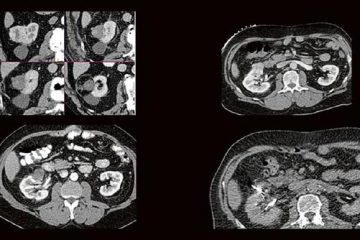

Die technischen Fortschritte bei der Entwicklung neuer Ultraschallgeräte (hochfrequente Ultrabreitband-Linearschallköpfe, Matrixsonden, Verfahren zur Beurteilung der Mikrovaskularisation) sowie Verbesserungen bei der Darstellung von Punktionsnadeln haben in den Gebietender Neurologie, Schmerztherapie, Unfallchirurgie/Orthopädie und Anästhesiologie in den letzten Jahren die Anwendungsbereiche der hochfrequenten Sonographie erheblich erweitert. Unser Anwenderseminar, welches zum 5. Mal ausgerichtet wird, Weiterlesen…